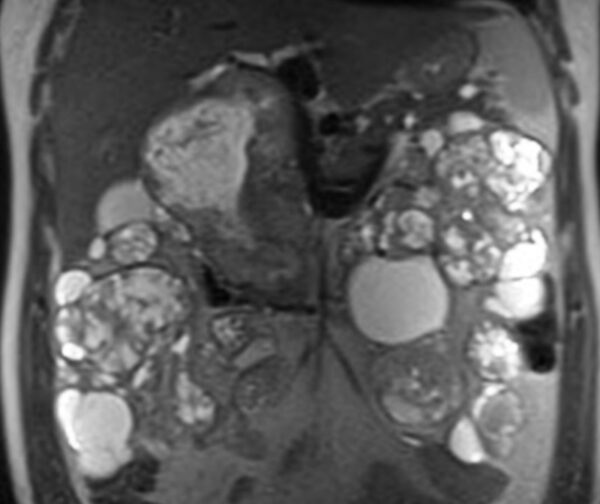

https://radiopaedia.org/cases/von-hippel-lindau-disease-20

MRI

GIT, GUT